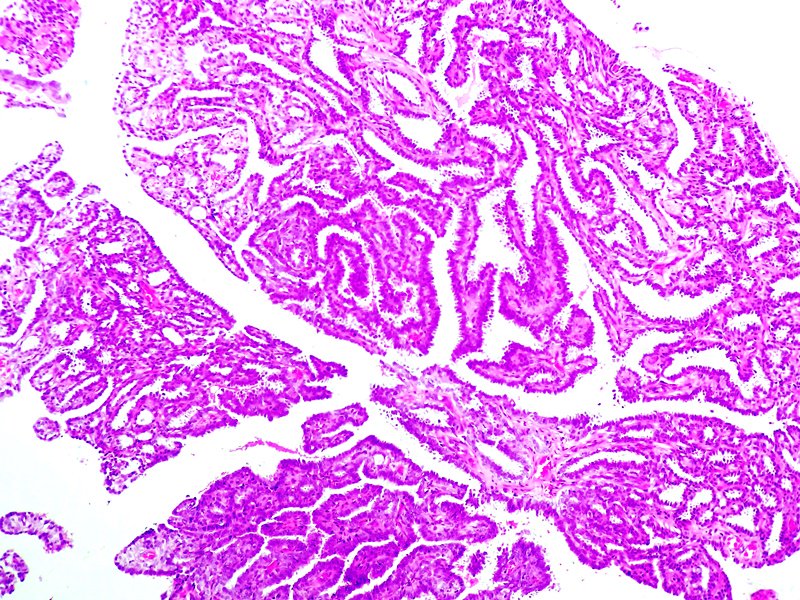

Epidídimo. Cistadenoma papilar. Tinción HE